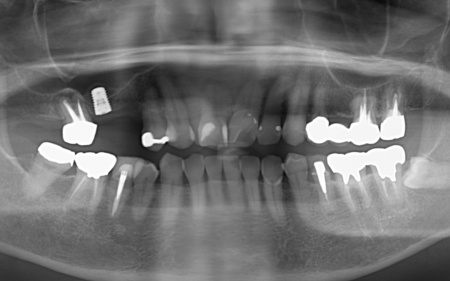

約2ヶ月後、インプラントと骨が結合したことを確認して、右上奥歯2本の仮歯を作製し、手前の歯槽骨が再生するまで経過観察を継続します。

約4ヶ月後、歯槽骨の再生が確認できたため、もう1本のインプラントを埋入しました。

右上奥歯は2本とも骨の高さが不足していたので、治療の際はソケットリフトを併用しています。

右上奥歯2本に仮歯が入り、噛み合わせが安定した状態になったため、根尖病巣を発症している右上奥歯の治療を開始します。

もともと入っていた古い被せ物を除去すると、歯根に亀裂が入っていました。こちらも歯の温存が難しいと判断し、抜歯処置を行いました。

最後に、完成した人工歯を装着し、見た目や噛み合わせに問題がないことを確認して、治療を終了しています。